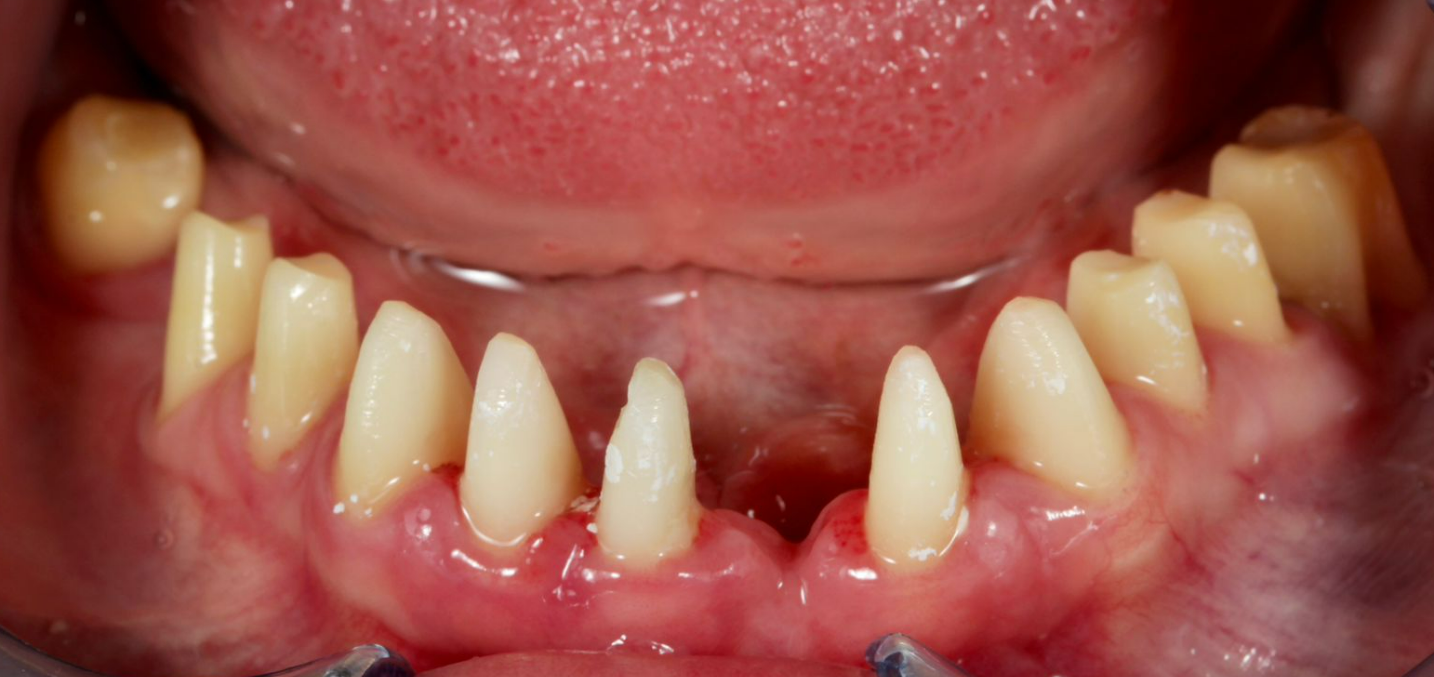

Periodontal status: Significant periodontal pathology was noted: deep periodontal pockets, along with supra- and subgingival calculus and plaque. Grade II tooth mobility was diagnosed in the maxilla; localized deep periodontal and bony defects were observed in specific segments of the mandible. Functional overload caused by a prognathic bite was also detected.

Mandible: Despite Grade I-II tooth mobility, taking the patient’s wishes into account, it was decided to preserve her natural teeth as much as possible. Only tooth 3.1 was indicated for extraction. Prosthetic restoration of the lower jaw was performed using prepared teeth with preserved vital roots.